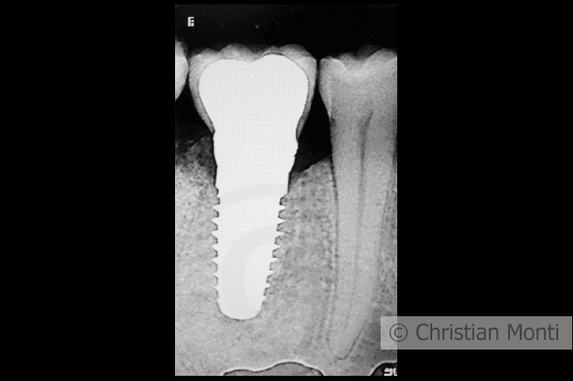

EDENTULIA SINGOLA

Impianto dilazionato in sostituzione di un molare inferiore